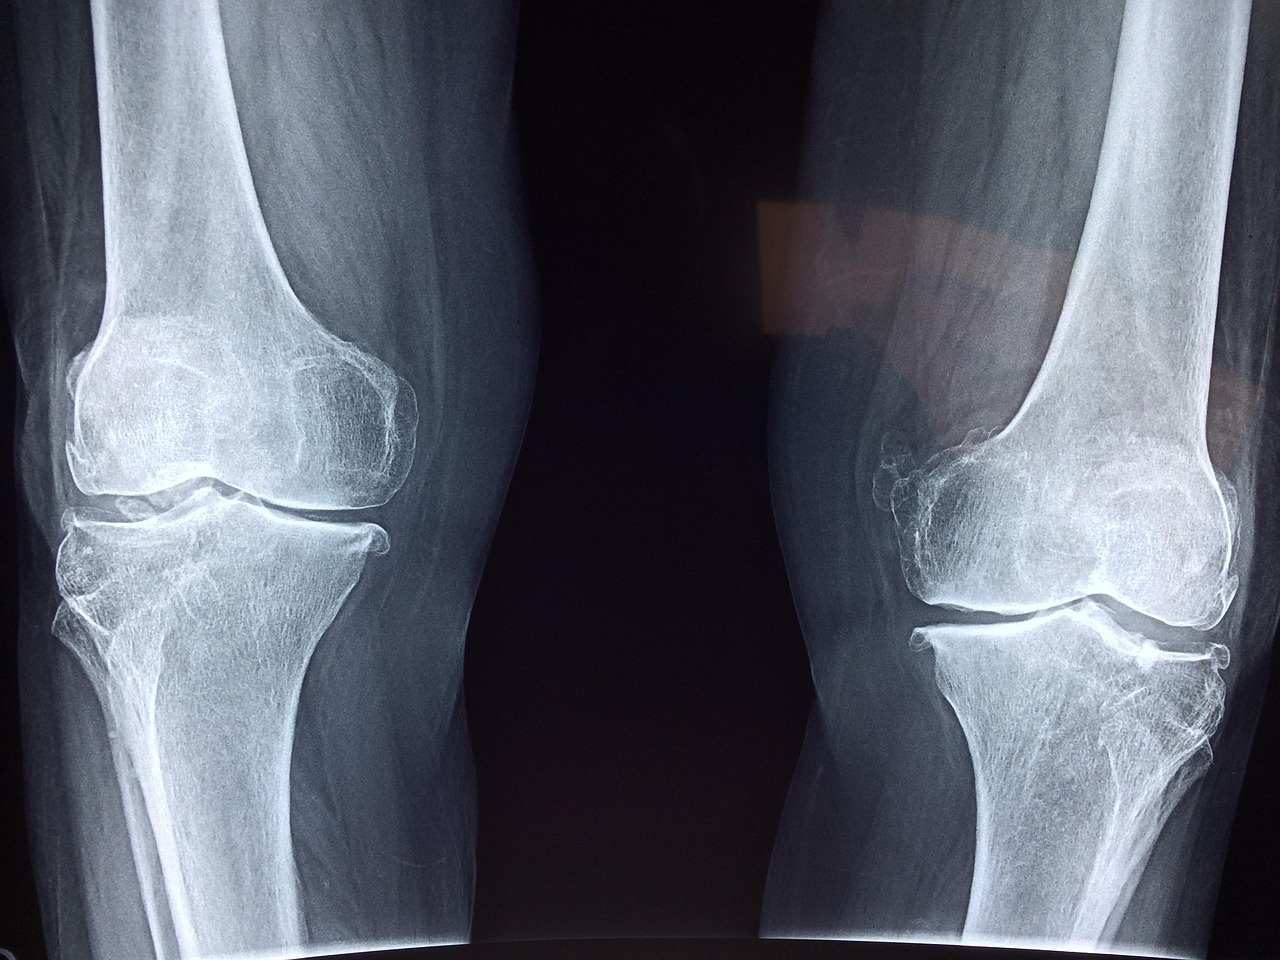

Präoperative Volumenmodelle und chirurgische Führungsplatten für verbesserte Operationsergebnisse

Die Fähigkeit, patientenspezifische anatomische Modelle vor einer Operation anzufertigen, revolutioniert die präoperative Planung in der Orthopädie. Anstatt sich nur auf zweidimensionale Röntgen- oder CT-Bilder zu verlassen, können Chirurgen mittels realitätsgetreuer 3D-Volumenmodelle die komplexen räumlichen Beziehungen von Knochen, Gelenken und Weichteilen besser verstehen.